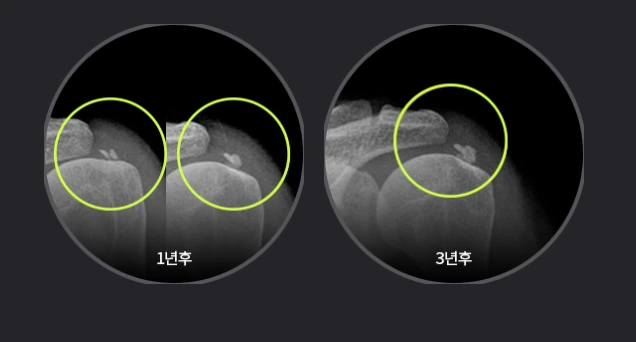

김태겸 원장님“일단 한 번 회전근개파열이 발생하면 시간이 지날수록 파열 크기가 증가 되기 때문에 힘줄 조직이 남아있을 때 부분적인 봉합이라도 해야 관절염이나 어깨 운동 마비 상태로 진행되는 것을 막을 수 있다”라고 강조하시네요.

에이스병원에서는 관절내시경을 통해 브릿지 이중 봉합술, 타가 및 자가 힘줄이식술, 역행성 인공관절 치환술 등 선별적 수술을 시행합니다.